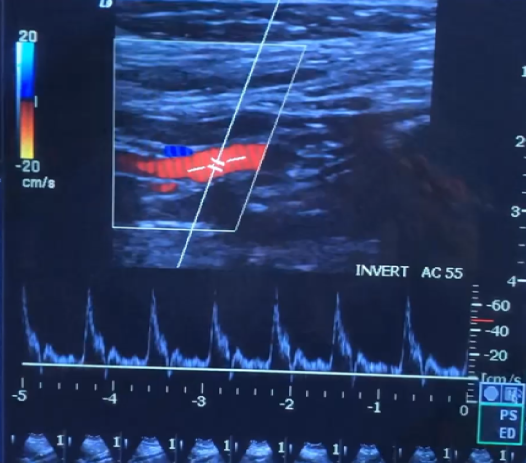

Based on the waveforms, Which vessel do they belong to?

ICA

Identify the vessel